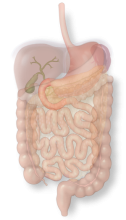

The duodenum is a C-shaped tube that receives food from the stomach and prepares it for chemical digestion further along in the intestines.

The colon is a large tube that stores feces and also contains helpful bacteria that breaks down food that has not yet been absorbed.

The stomach is a muscular sac that is important for absorbing food and preparing food for further digestion.

The liver is a solid organ that produces bile for fat digestion and is also the first stop for the majority of absorbed nutrients.

The pancreas is a gland that produces chemicals for food break-down as well as a hormone system that regulates sugar.